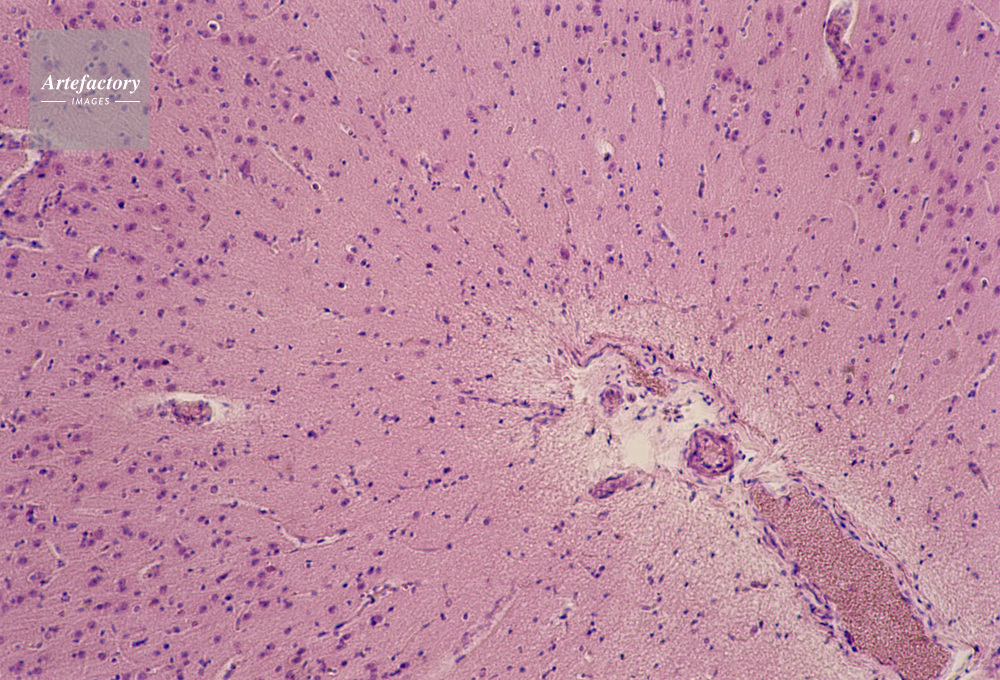

| キャプション | 大脳組織,100倍 | 制限事項 | ||

| ソース | ピクセル数 | 5553px × 3775px | ||

| 撮影地 | 印刷サイズ | 30.3cm × 20.6cm | ||